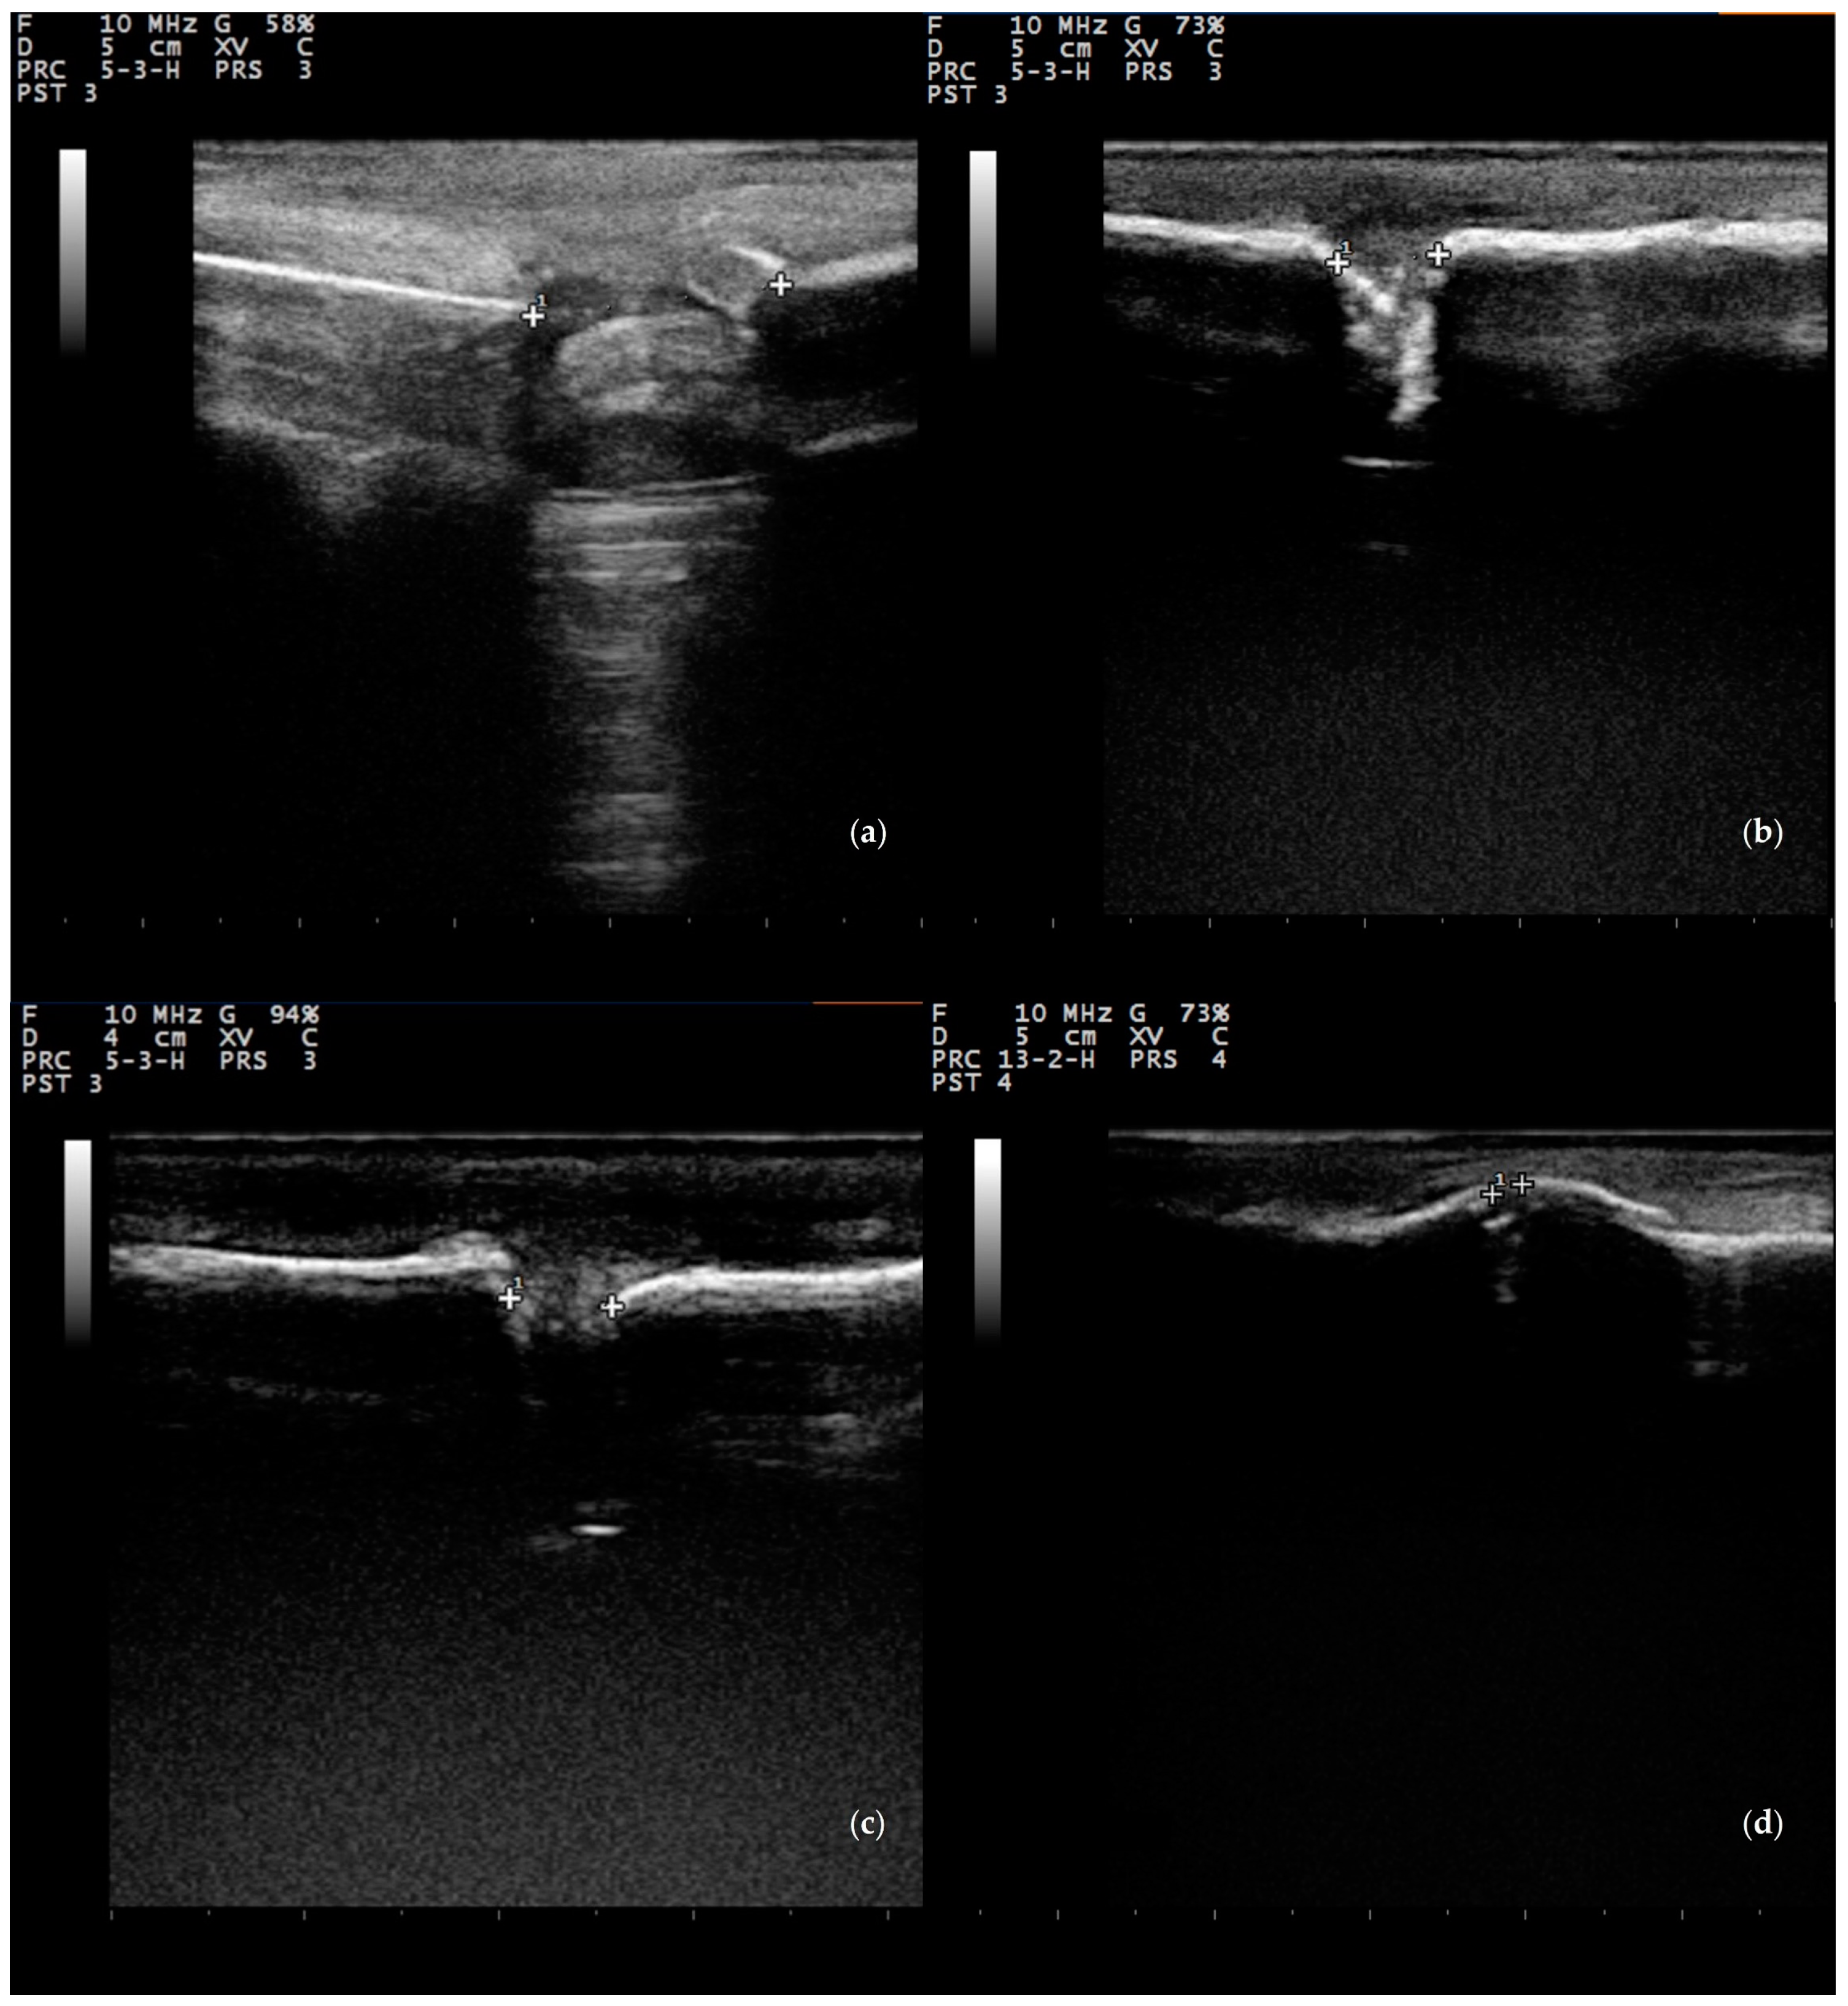

3.3.2. Ultrasonographic Examination

- Maffulli, N.; Thornton, A. Ultrasonographic appearance of external callus in long-bone fractures. Injury 1995, 26, 5–12. [Google Scholar] [CrossRef]

- Risselada, M.; Kramer, M.; De Rooster, H.; Taeymans, O.; Verleyen, P.; Van Bree, H. Ultrasonographic and radiographic assessment of uncomplicated secondary fracture healing of long bones in dogs and cats. Vet. Surg. 2005, 34, 99–107. [Google Scholar] [CrossRef] [PubMed]

- Risselada, M.; Van Bree, H.; Kramer, M.; Duchateau, L.; Verleyen, P.; Saunders, J.H. Ultrasonographic assessment of fracture healing after plate osteosynthesis. Vet. Radiol. Ultrasound 2007, 48, 368–372. [Google Scholar] [CrossRef]